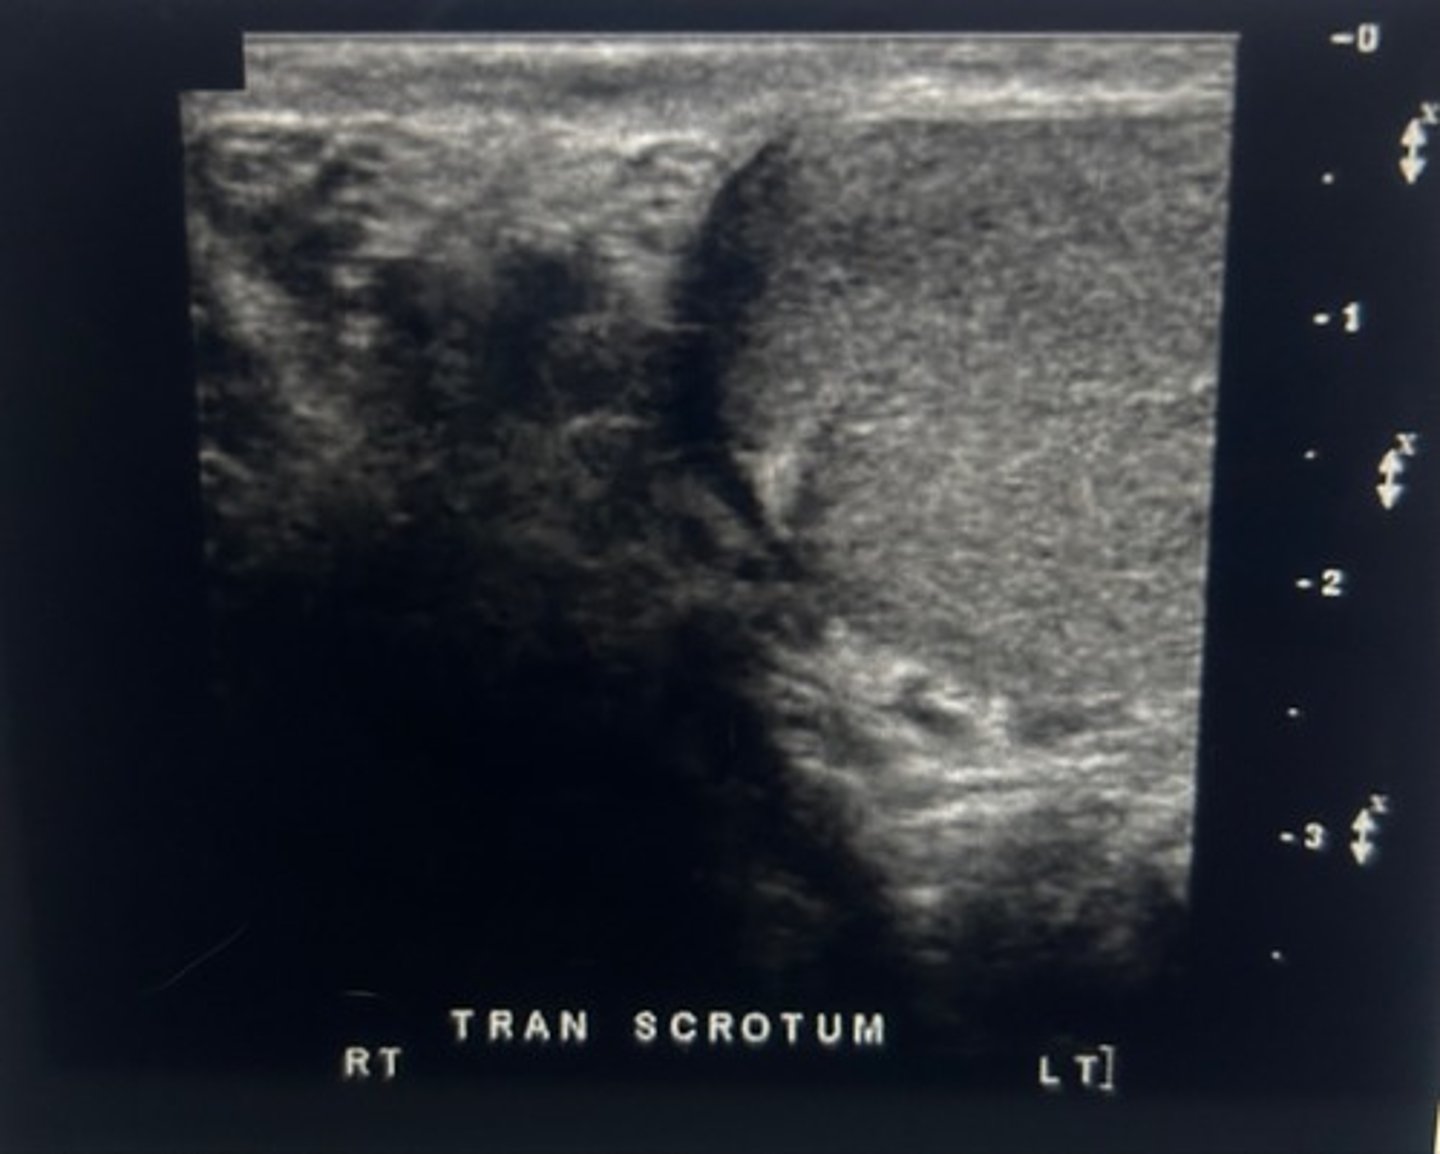

When using color Doppler to compare, testicular perfusion, you should always

use the dual screen function to demonstrate an image of both testicles